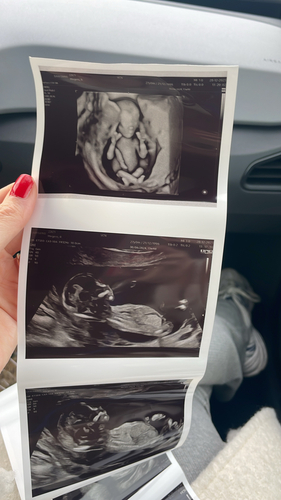

13.3 hier. Is hier een nub te zien? 💗💙

Iemand enig idee? Ben benieuwd 🥰

13+4 weken.. Kan iemand iets zien? Ik vind het zelf erg lastig om te bepalen waar de nub zit